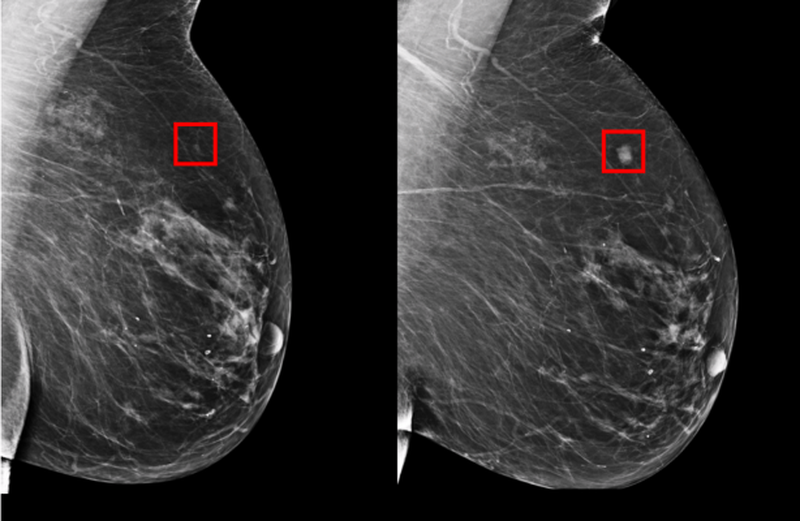

MIT’s Computer Science and Artificial Intelligence Lab has developed a new deep learning-based AI prediction model that can anticipate the development of breast cancer up to five years in advance. Researchers working on the product also recognized that other similar projects have often had... Read full article...